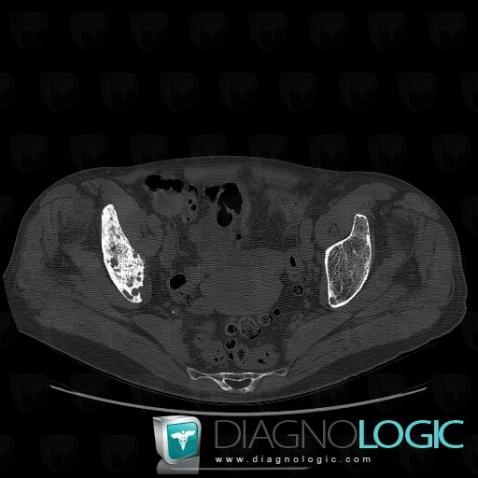

Metastasis, Ilium, CT

Here is the specific information in the key image above:

- Diagnosis Metastasis, Location(s) Ilium, with gamuts Well-defined osteolysis